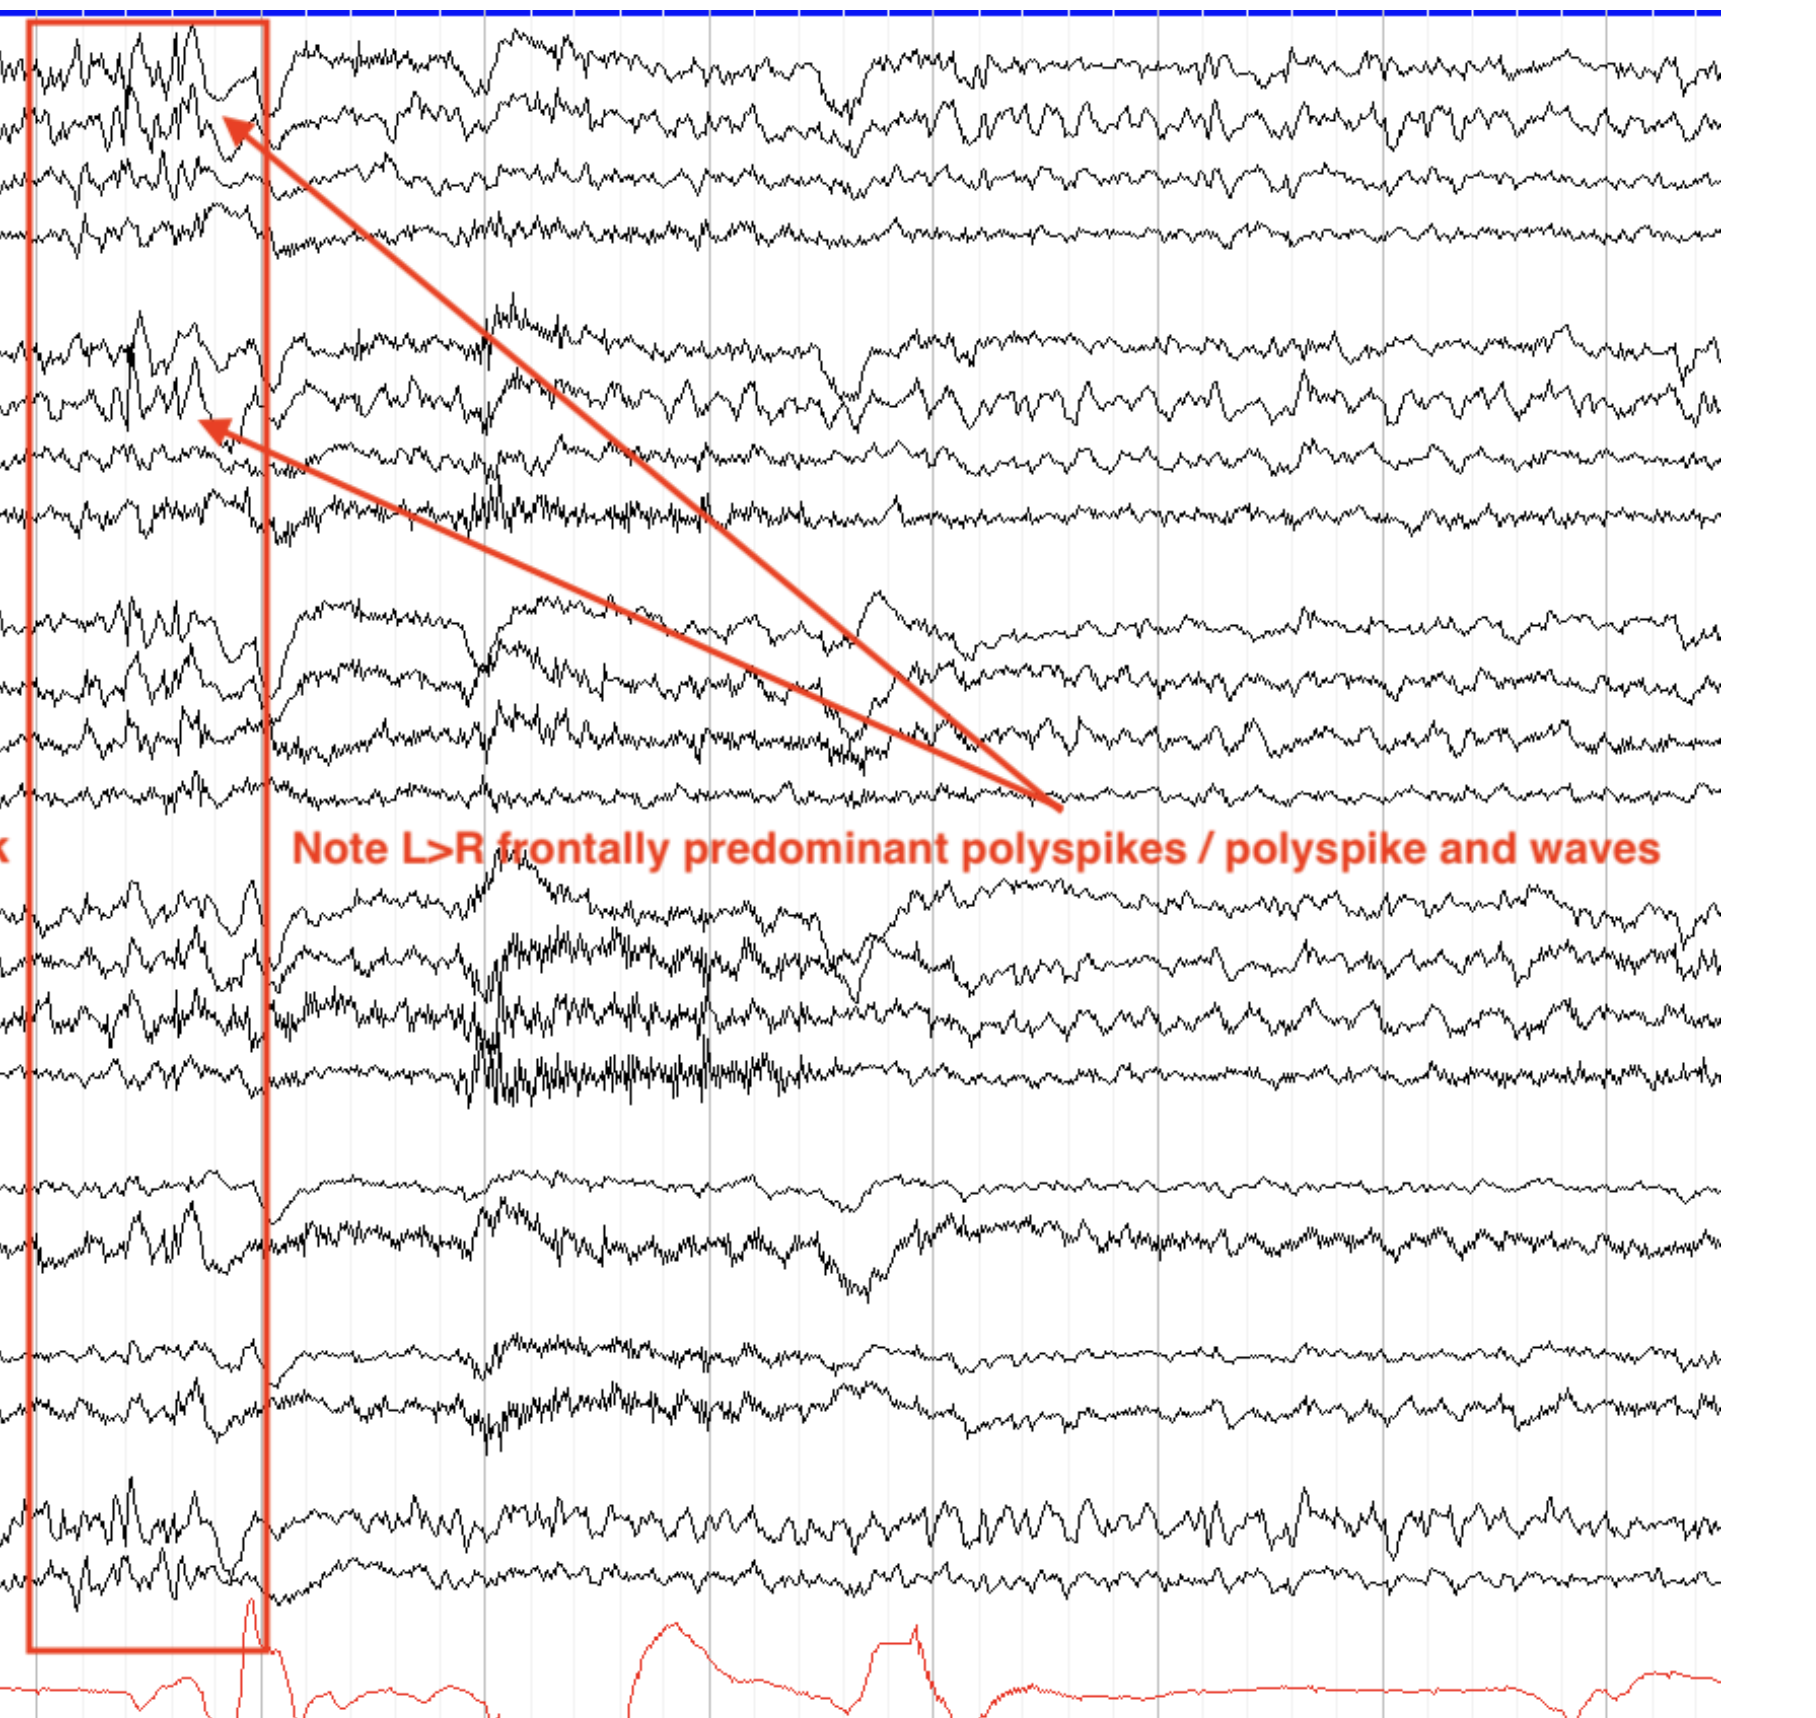

polyspikes/brief

myoclonic jerk